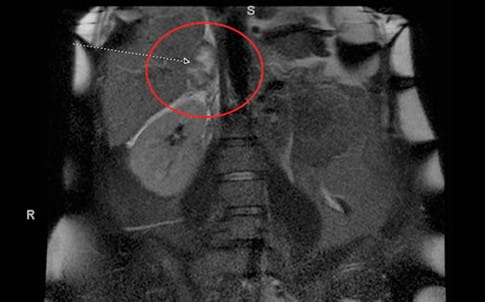

A 28-year-old female with a history of irritable bowel syndrome (IBS) and asthma presented to a UPMC emergency room with nausea, vomiting, and right sided abdominal pain during the 35th week of her first pregnancy. An abdominal MRI revealed a 4.7 x 2.8 cm right adrenal hemorrhage (see Image 1).

Image 1: MRI without contrast remarkable for a 4.7 x 2.8 cm indeterminate right adrenal lesion with associated perinephric fluid. This finding is concerning for adrenal hemorrhage.